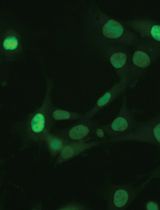

Circulating anti-dsDNA antibody is a hallmark of SLE both in human patients and in many SLE mouse models. This protocol describes how to measure the frequency of plasma cells producing these antibodies in the spleen of lupus-prone mice. This protocol was developed or modified in Dr. Anne Davidson’s lab at Feinstein Institute for Medical Research.

Liu, Z. (2011). ELISpots Assay to Measure the Number of Murine Plasma Cells Producing Anti-dsDNA Antibodies. Bio-protocol 1(24): e34. DOI: 10.21769/BioProtoc.34.